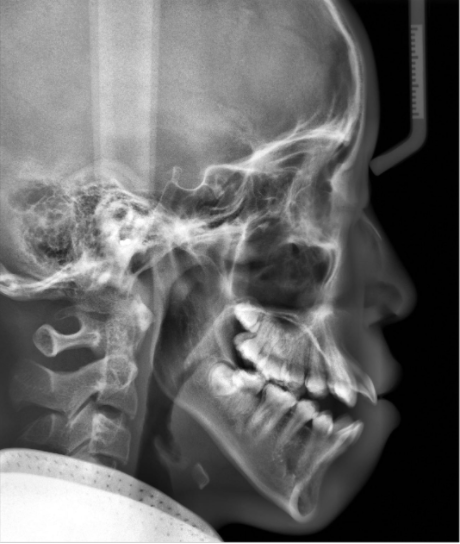

5、后牙锁颌、偏颌、开颌问题

由于孩子的不良习惯或乳尖牙引导等因素,部分孩子在乳牙列完整萌出后,会出现后牙锁颌伴下颌功能性偏斜,这种情况相对严重且容易被忽略。

还有因遗传、吮指、吐舌、咬硬物,以及磨牙过度萌出等因素导致的开颌问题,也不要忽略,不仅会引起饮食上的不便,危害孩子关节的健康,主要影响说话发音清晰问题,甚至导致面型出现下巴后缩。

如果在定期的面诊检查中发现问题,可以在替牙初期或者替牙期阶段及时干预,可以引导颌骨发育恢复正常。